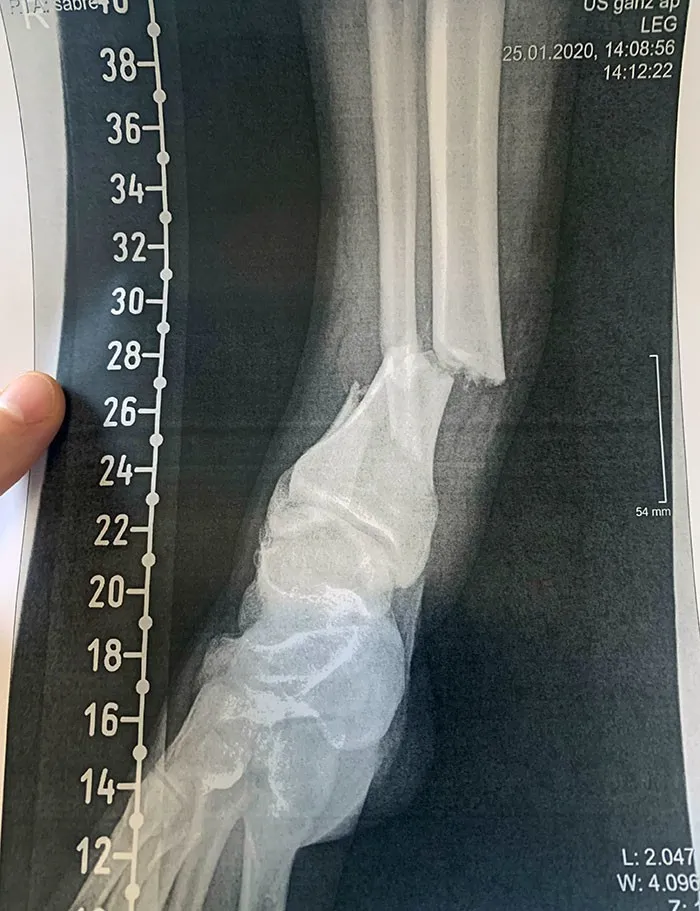

14. "Я наступил на LEGO и сломал лодыжку"